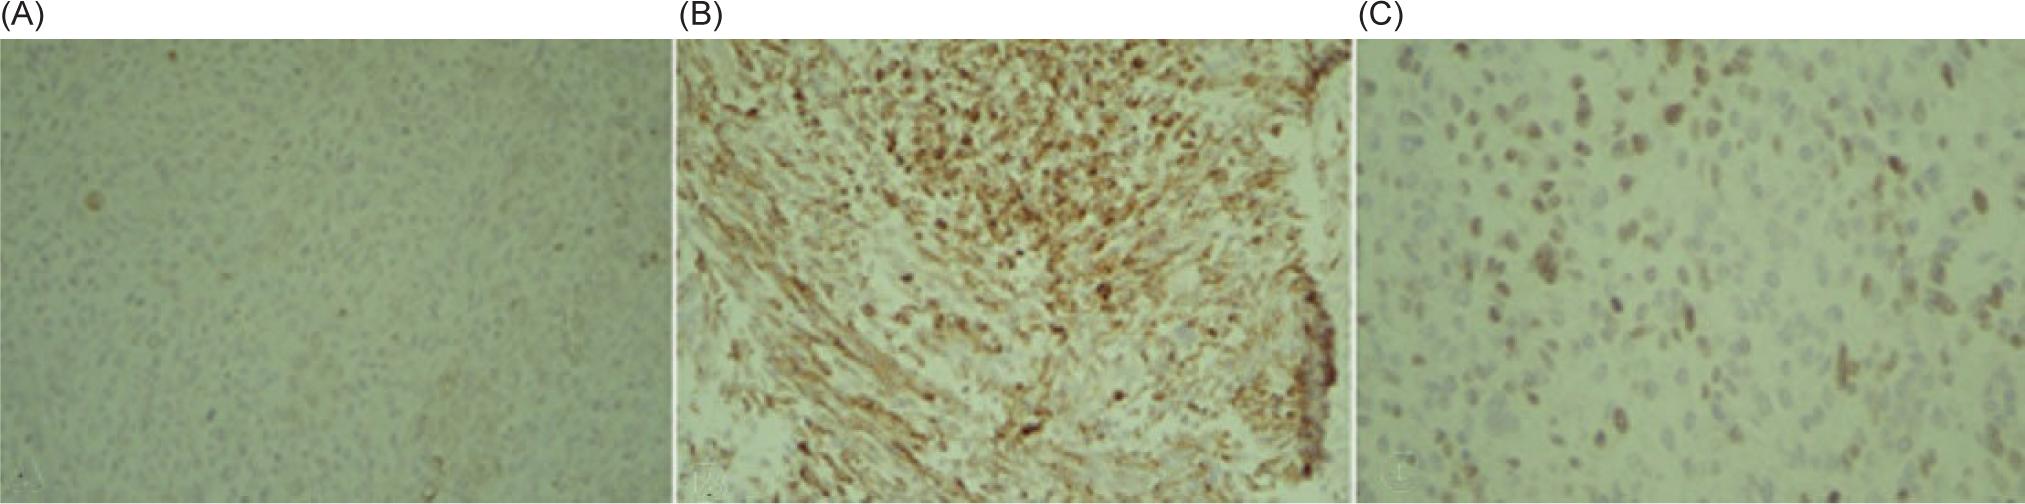

The patient underwent a right radical nephroureterectomy. Histopathology examination studies confirmed the diagnosis of RMS with a pleomorphic component that was limited to the kidney. The ureter, perinephric fat, adrenal gland, and vascular margin were free of tumor. There were no lymphovascular invasions. However, tumor necrosis was presented. Light microscopy disclosed a malignant tumor made up of large, haphazardly arranged cells of various shapes with abundant, intensely eosinophilic cytoplasm. Cytoplasmic cross-striations were discovered in the spindle and tadpole-shaped cells. There were different mitotic figures and necrotic areas (Figur 2). Immunohistochemistry revealed that myogenin, smooth muscle actin (SMA), and desmin stained positively, but cytokeratin, EMA, CD10, S100 protein, and vimentin stained negatively. These findings indicated that the tumor arose from the skeletal muscle, leading to the right kidney and the final diagnosis of pleomorphic RMS (Figure 3).

Figure 3: Immunohistochemistry positive reaction for (A) Creatine kinase. (B) Desmin. (C) Myogenin.